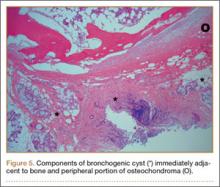

The fluid culture grew mixed flora, with no Staphylococcus aureus, group A streptococcus, or Pseudomonas aeruginosa identified. The pathologic examination identified bone with a cartilaginous cap, consistent with osteochondroma (Figure 3), as well as a cyst lined by respiratory epithelium with patchy areas of squamous epithelium and surrounding mucus glands, consistent with bronchogenic cyst (Figure 4). Figure 5 shows the contiguous nature of the 2 lesions.